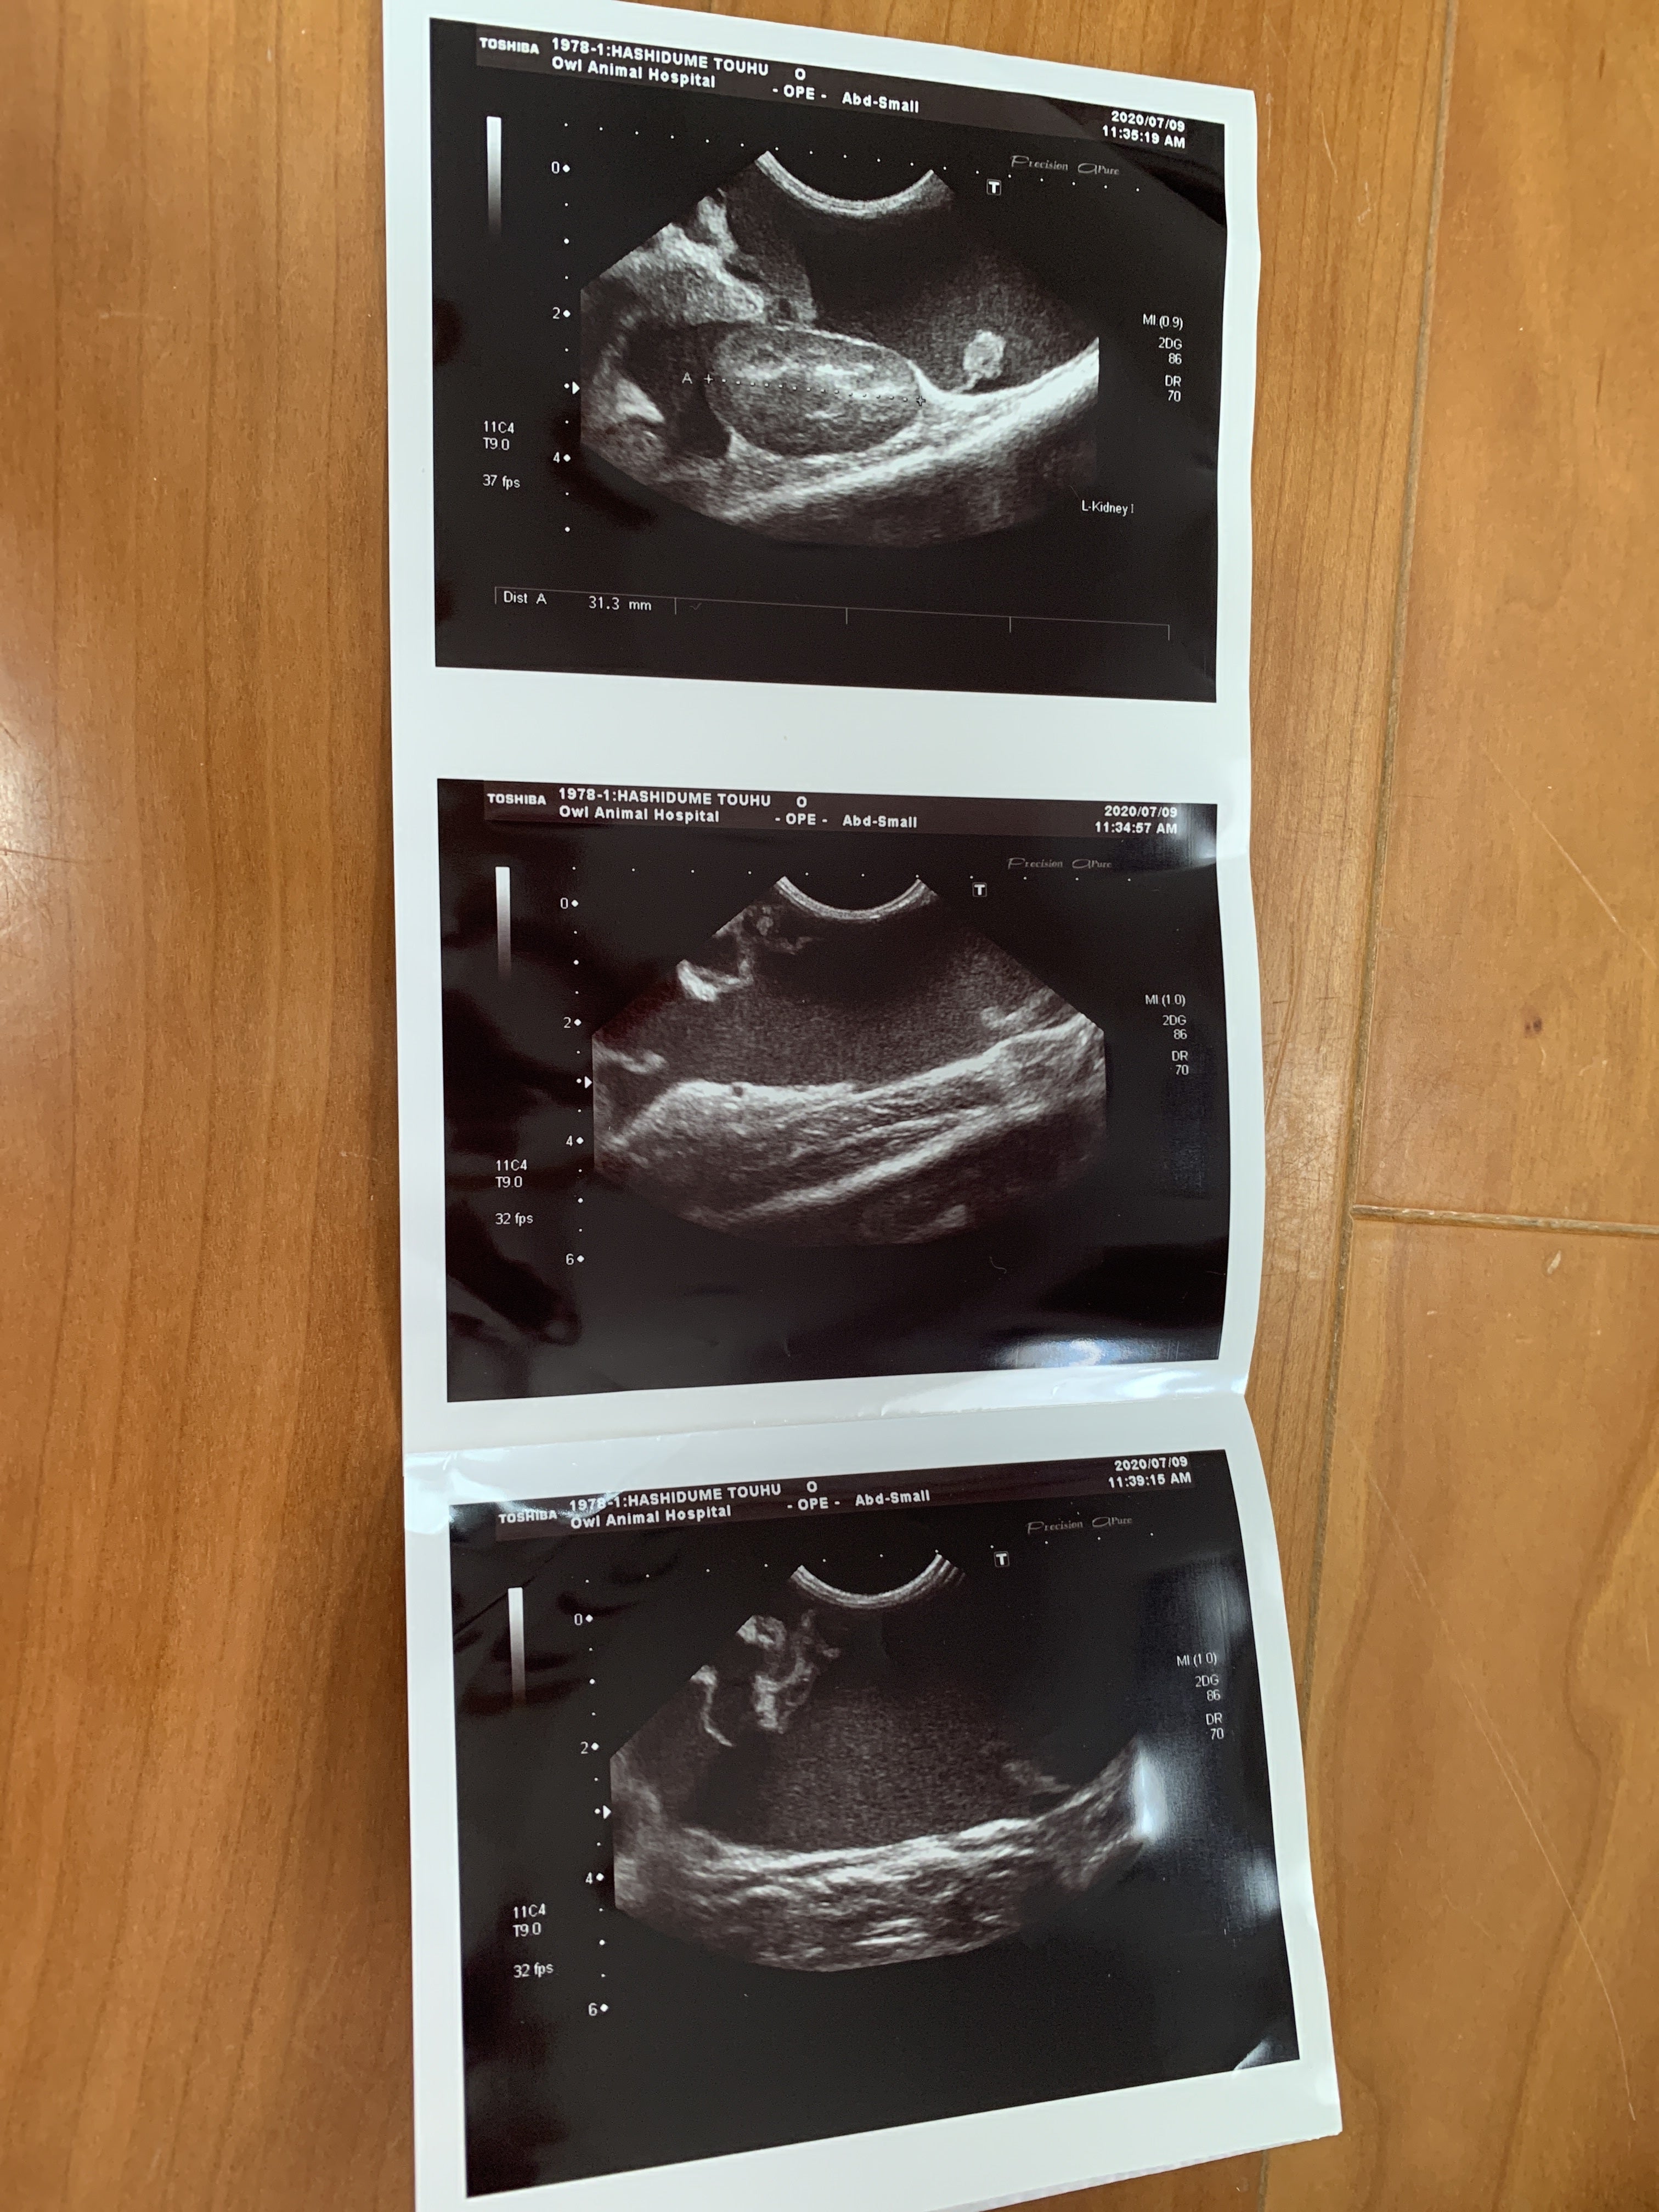

7月9日 朝から病院に連れて行きました。血液検査とエコーの結果

ここで初めて猫伝染性腹膜炎かも知れないと言われました。少しお腹が膨らんでいるのは便秘ではなく腹水でした。私は初めてその病名を聞きました。先生が言うには、このFIP と言う病気は進行が早く数日〜2か月で亡くなる怖い怖い病気ですとの事でした。その後の先生の話を涙が流れるのを必死にこらえて聞いていました。

ますます腹水が増えてきています